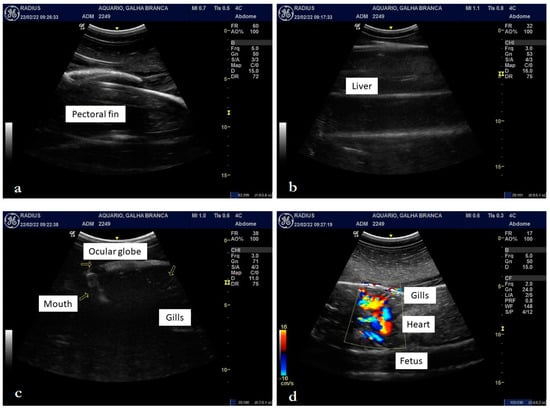

Ultrasound Examination

3.2. Internal Morphology